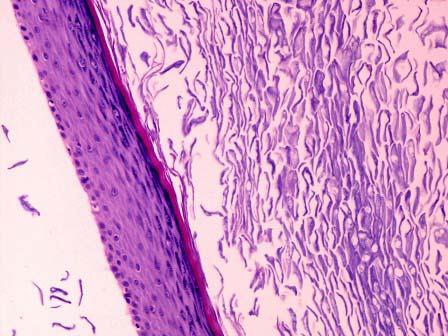

如图,背部皮下肿块切除,病理诊断为“表皮囊肿”,镜下见真皮内异位鳞状上皮角化,形成囊肿,囊肿部分破裂,巨噬细胞等围绕形成结节(如图所示)。此结节病变应称 ...

问题 如图,背部皮下肿块切除,病理诊断为“表皮囊肿”,镜下见真皮内异位鳞状上皮角化,形成囊肿,囊肿部分破裂,巨噬细胞等围绕形成结节(如图所示)。此结节病变应称 ( )

选项 A.脓肿 B.结核结节 C.异物肉芽肿 D.机化 E.钙化

答案 C